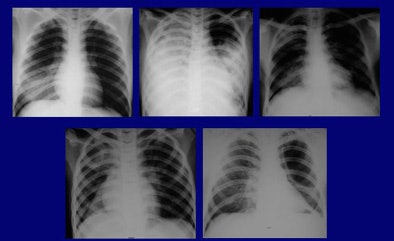

"Characteristically," Qureshi said, "the patients who died came in very sicker, got even sicker and died -- within nine days." The survivors, however, who were hospitalized for as long as 42 days, developed other complications -- pleural effusions and cavitations or areas of deep-seated infections, she said.

| The H5N1 avian flu virus is endemic in the poultry stocks of nine Southeast Asian countries. Chest x-rays of patients infected with the virus may demonstrate focal consolidation, reticulonodular shadowing, pleural effusion and/or thickening, pneumothorax, lobar collapse, and lymphadenopathy. The appearance and pathological progression of disease on chest x-rays differed between patients who succumbed to avian flu (above) and those who survived infection (below), primarily in terms of continued progression among nonsurvivors, and in the total number of involved segments. Evidence of consolidation in four or more lung segments was significantly associated with mortality. Survivors and nonsurvivors alike were all treated with broad-spectrum antibiotics and the antiviral drug Tamilflu (Roche, Basel, Switzerland). All images courtesy of Dr. Nagmi Qureshi. |